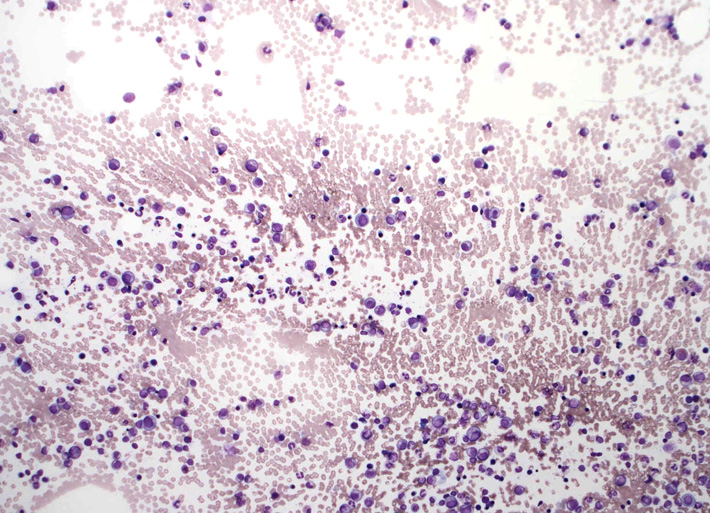

骨髄スメア標本です。ねっとりした血清成分がよくわかります。「hyperviscosity」の状態= 過粘稠(ねんちゅう-と読む)症状; hyperviscosityの正しい訳は過粘度のほうがよいと思う.

赤血球が索状に連なる連銭形成rouleauxが明瞭。